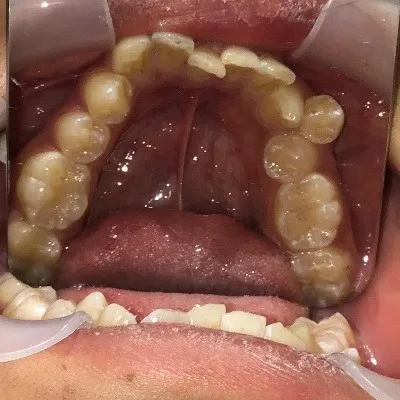

今回は他院さんでインビザライン矯正治療を受けていた患者様を引き継いで当院でインビザライン治療を継続した症例をご紹介致します。

今回はマウスピース矯正を主軸にした矯正ですが、一部ワイヤー矯正も併用して改善しております。